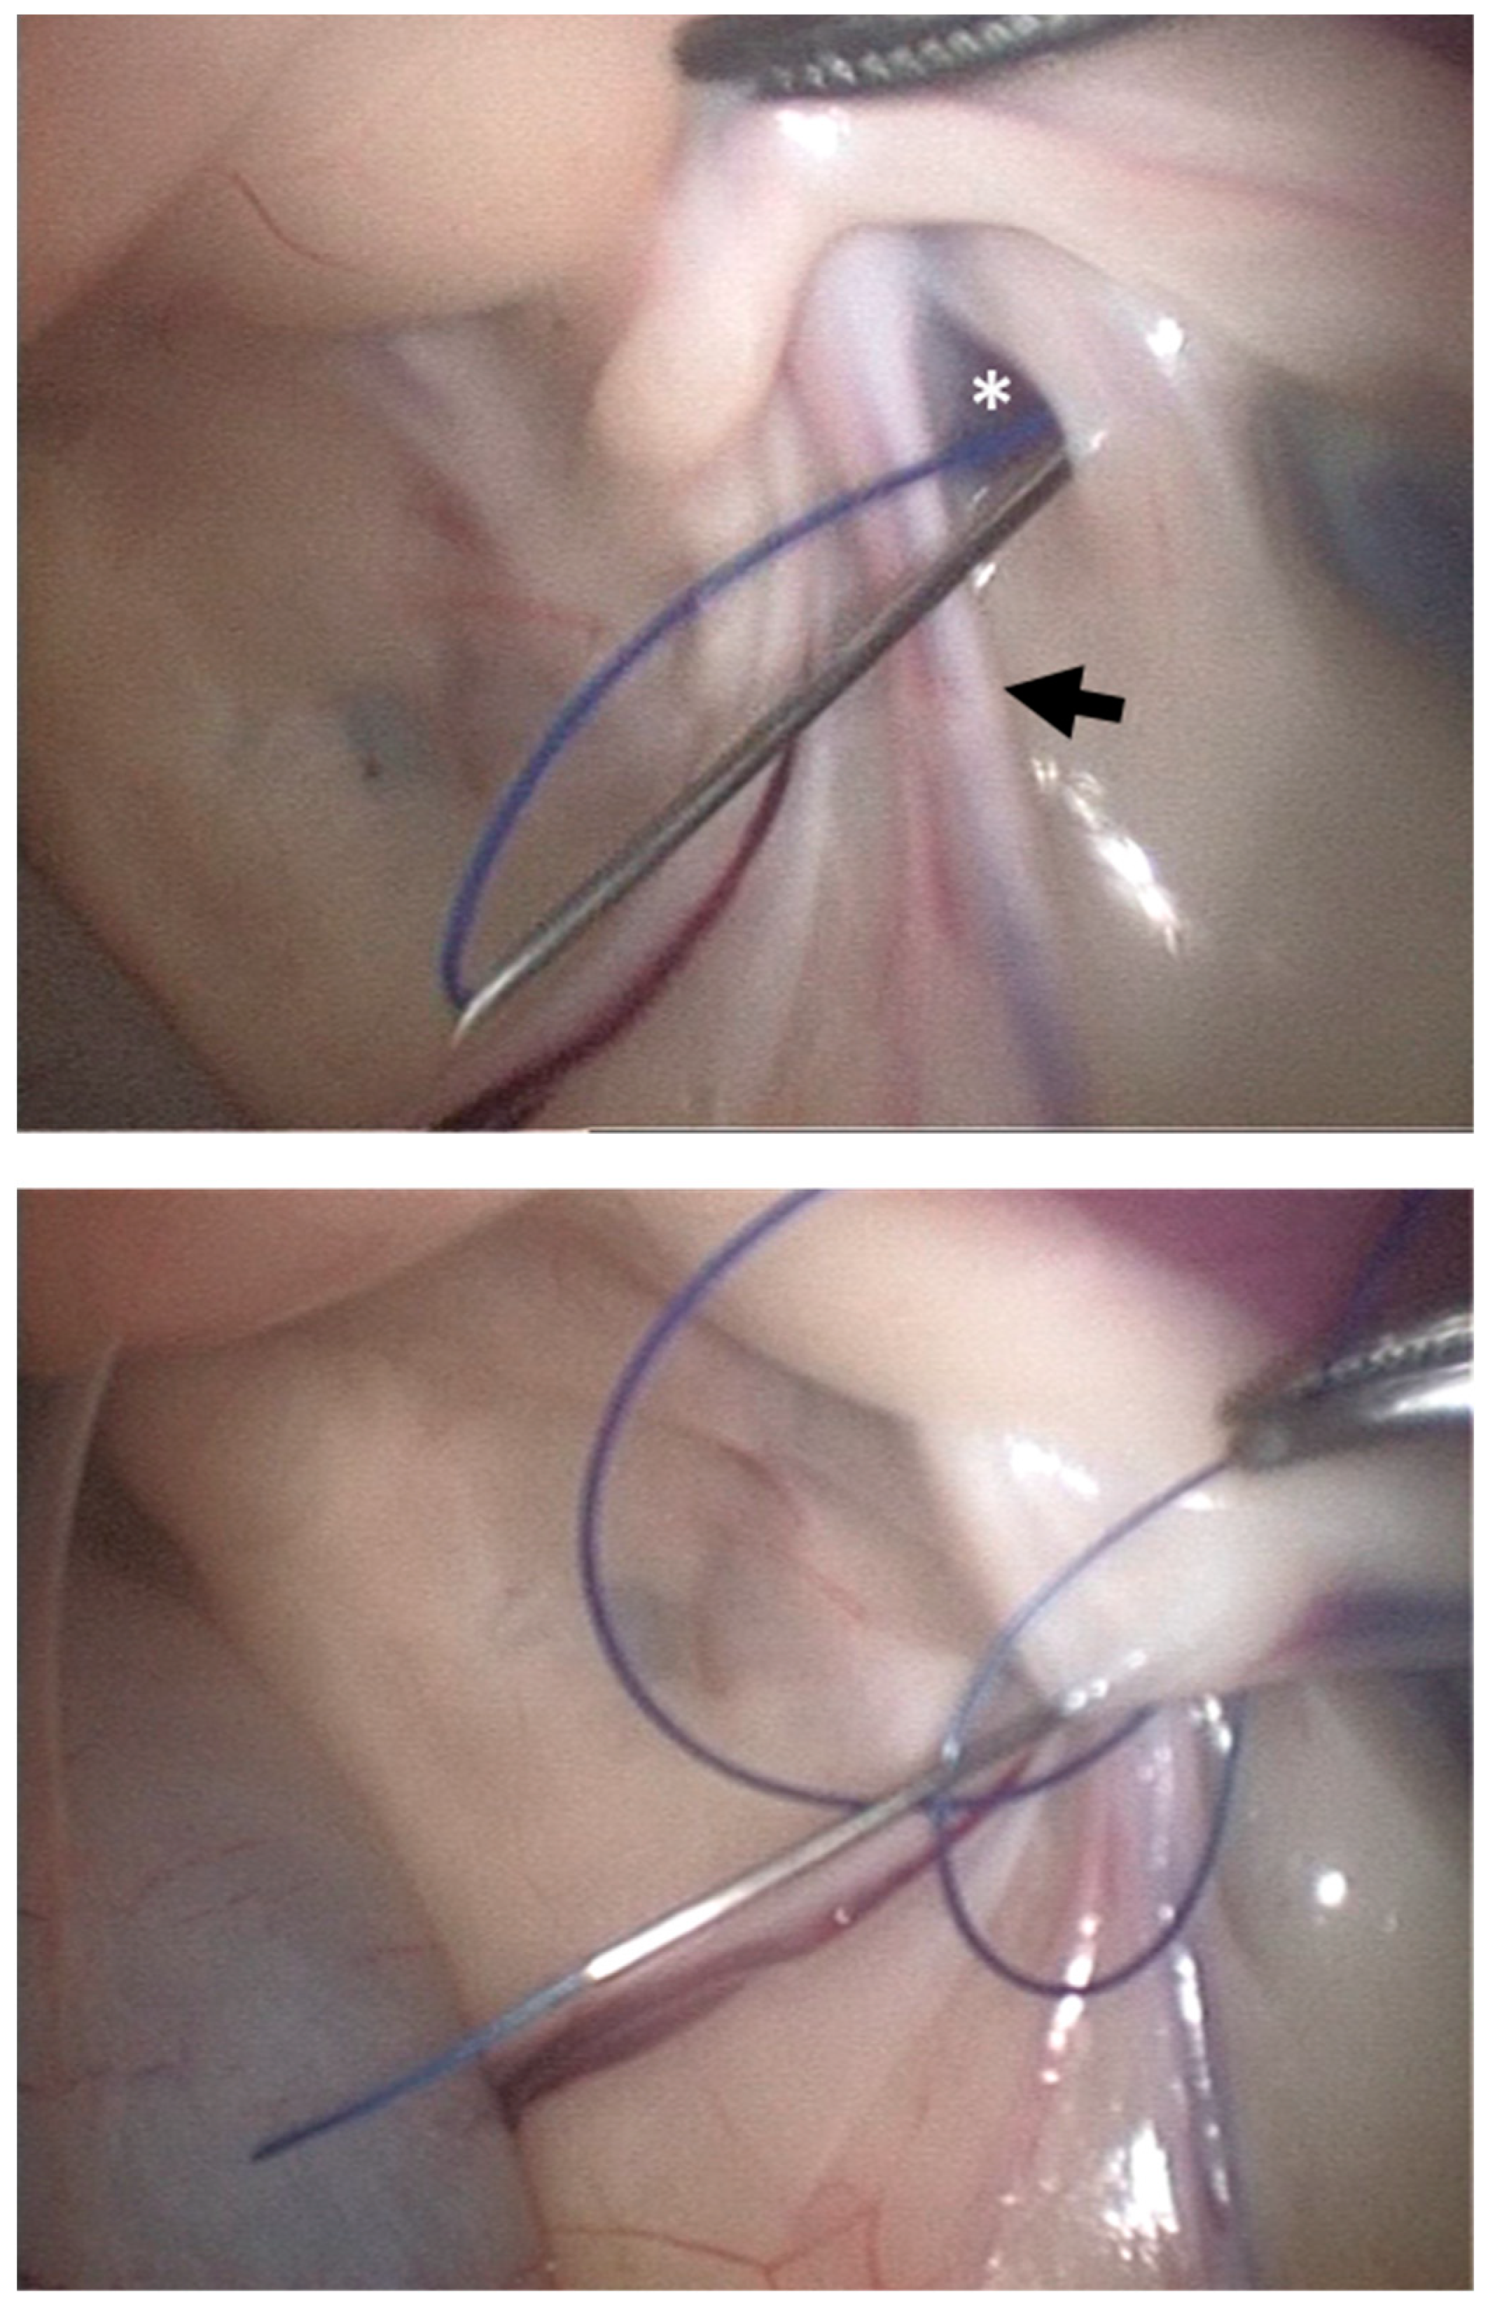

2.1.2. LAPS Surgical Procedure

2.1.3. Assessment of IIR Partial Closure